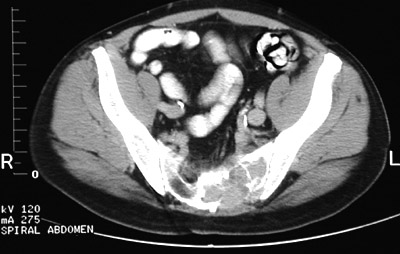

This pelvic CT scan demonstrates osteolytic metastases extending from the sacrum across the sacroiliac joint on the left. In this case, the primary neoplasm was a renal cell carcinoma.